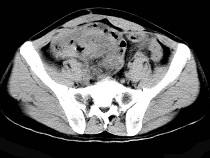

问题 58岁,间断腹部隐痛9个月,贫血3个月,近日加重并伴有柏油样便,CT所见如图,最可能诊断是()

选项 A.小肠淋巴瘤 B.小肠恶性间质瘤 C.小肠重复畸形 D.小肠癌 E.小肠淋巴肉瘤

答案 E